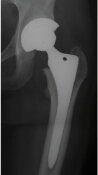

右変形性股関節症の方です。手術前は非常に痛みが強く足をしっかりつけませんでしたが、手術後痛みは楽になり1週間で杖歩行が可能となりました。3週間では杖なしでスムースな歩行ができるようになりました。